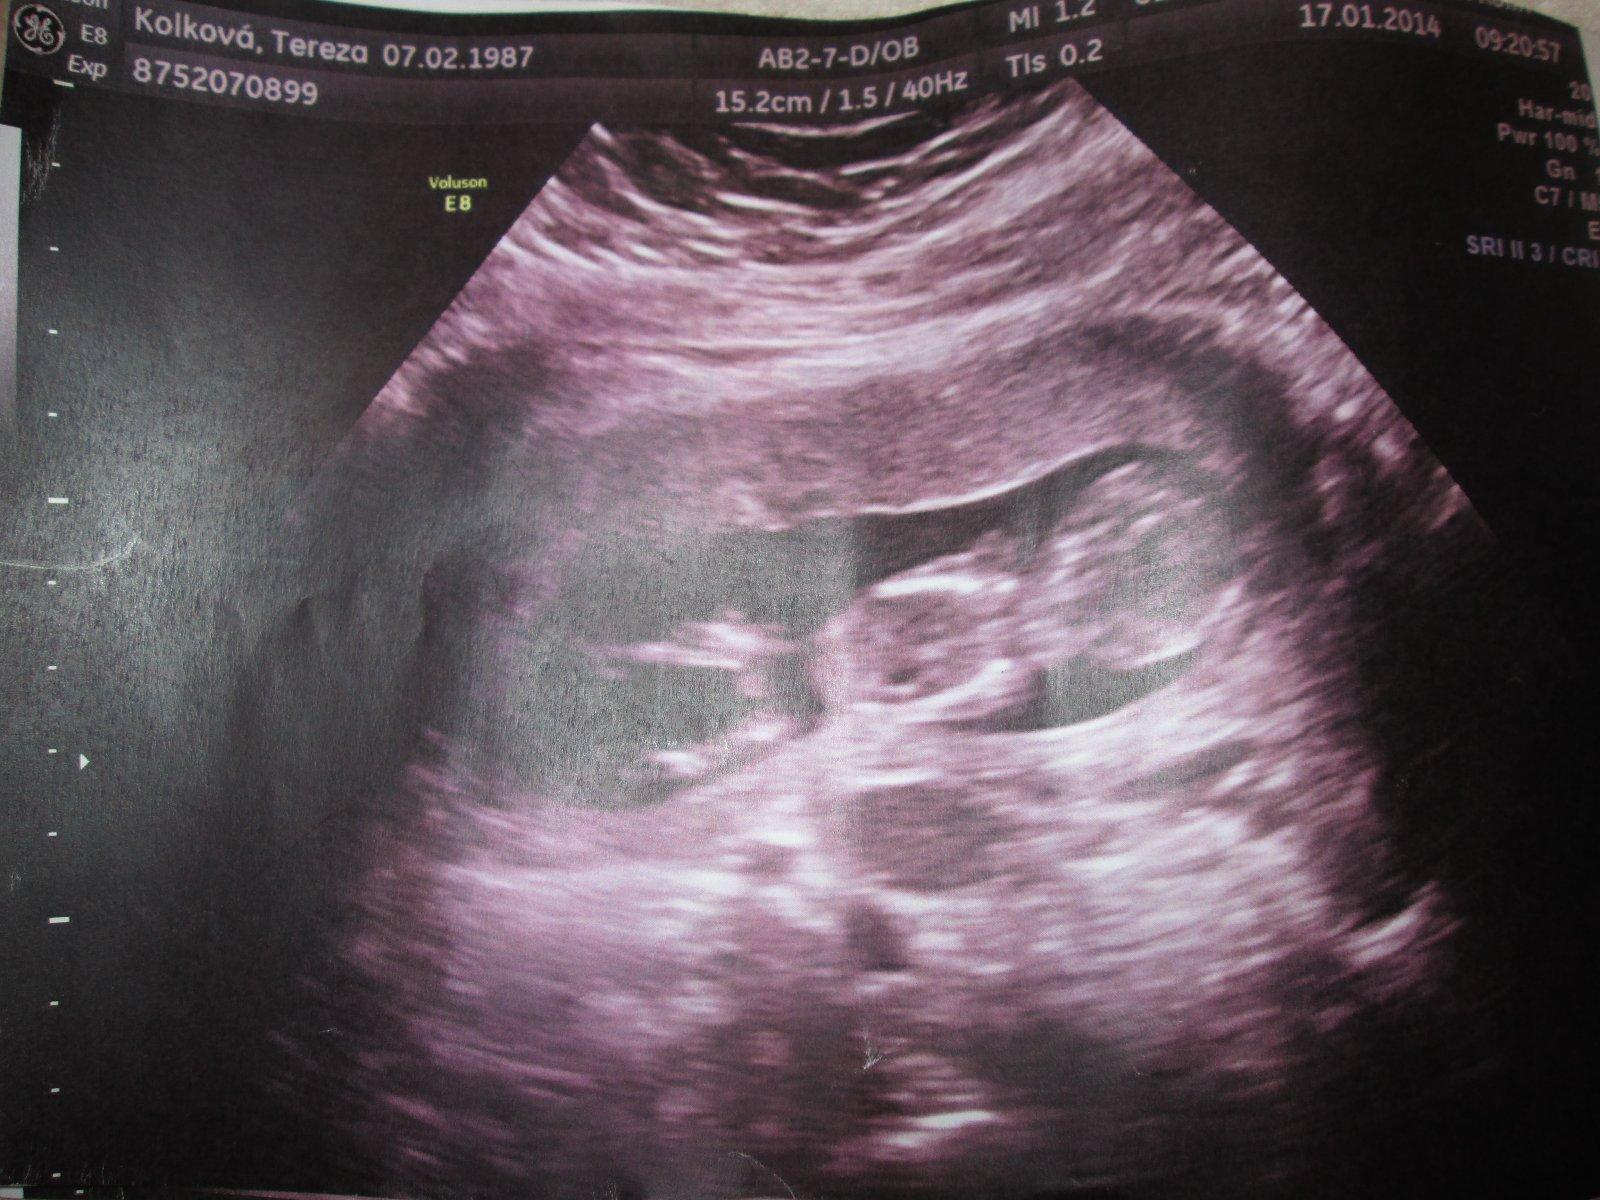

Je to holčička nebo chlapeček? Foto ultrazvuku

@relax84 podle mě je to holčička ;) mně ji potvrdili teda až ve 20tt, protože měla pořád nožky křížem, ale vypadá to takto

No já vidím opravdu jasnou holčičku 🙂 tady snad nekdo o zom pochybuje,mam 3syny a obrázky jsem měla jiné relax85,nvo jineho by bylo kdyby nebyly nozicky takhle od sebe,kdyby to byl klučík,tak by výrazně čouhalo něco dopředu , ;) 🙂